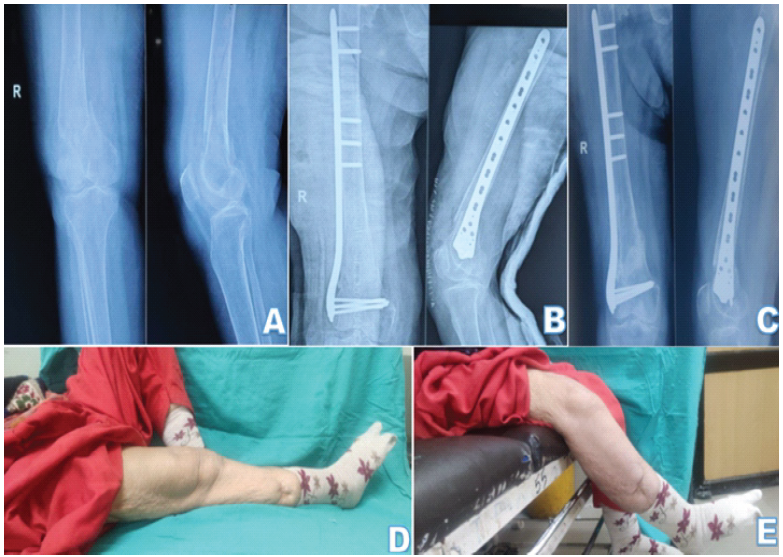

In LCP group, 43.5% patients were operated using MIPO, whereas in 56.5%, ORIF was used (Figs. 3, 4).

Figure 4: (a) Radiographs of a patient with fracture of right distal femur; (b) immediate post-operative radiographs of the same patient, managed operative by open reduction and internal fixation with distal femur locking plate; (c) follow-up radiographs after 1 year; (d) flexion deformity of 10° and (e) extensor lag of 60° at 1-year follow-up, which may be contributed by the advanced tricompartmental knee osteoarthritis of the patient.